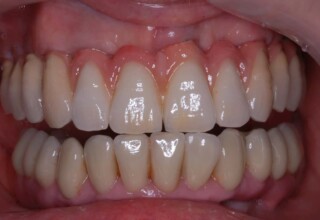

Composite Resin Veneers

Resin veneers are an inexpensive mode of esthetic improvement of anterior teeth, premolars also. Their potential is admirable and their limit is the operator’s clinical dexterity and imagination. In this case there were multiple problems with the upper four incisors: staining, poor inclinations, diastemas, multishading, poor interrelationship and poor tooth-gingiva ratios. They were restored with four direct composite resin veneers (one on a porcelain implant crown!) which were manufactured intraorally!!!